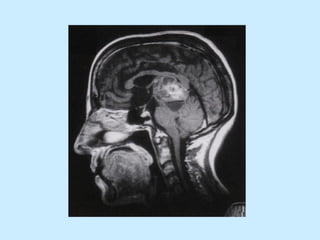

Dor neuropática central Incidência de 8% nos AVC. Ocorre mais freqüente nos infartos talâmicos .

Ocorre dor neuropática central em 75% dos pacientes com Seringomielia.

Ocorre dor neuropática central em 28% dos pacientes com Esclerose Múltipla

Dor neuropática centralIncidência de 8% nos AVC. Ocorre mais freqüente nos infartos talâmicos .

• 39.

Ocorre dor neuropáticacentral em 75% dos pacientes com Seringomielia.

• 40.

Ocorre dor neuropáticacentral em 28% dos pacientes com Esclerose Múltipla